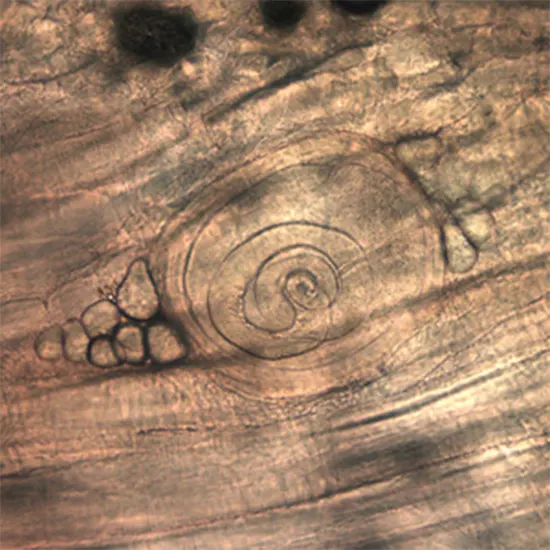

A nematode belonging to the genus Trichinella causes trichinosis. Throughout their life cycle inside their host, the parasites shift between skeletal muscle and enteric phases. When the host consumes the infected meat, the enteral phase of the life cycle starts

It is simple to misdiagnose the enteral phase since its symptoms are similar to those of other enteral illnesses. In severe infections, larvae are frequently found in muscle biopsy. The worms could be mistaken for pieces of muscle tissue if the biopsy is conducted before the larvae start to coil. When anti-Trichinella IgG antibodies are found, serology reveals a possible trichinosis infection.